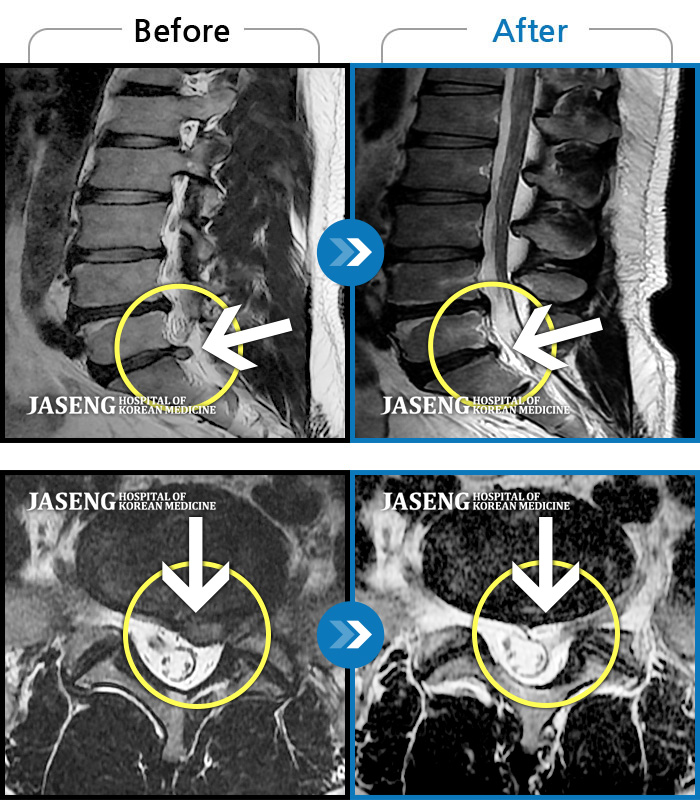

ȯںп Ǹ ǿ ԿǾ, ο ġ ۿ Ƿ ġḦ Ͻñ ٶϴ.